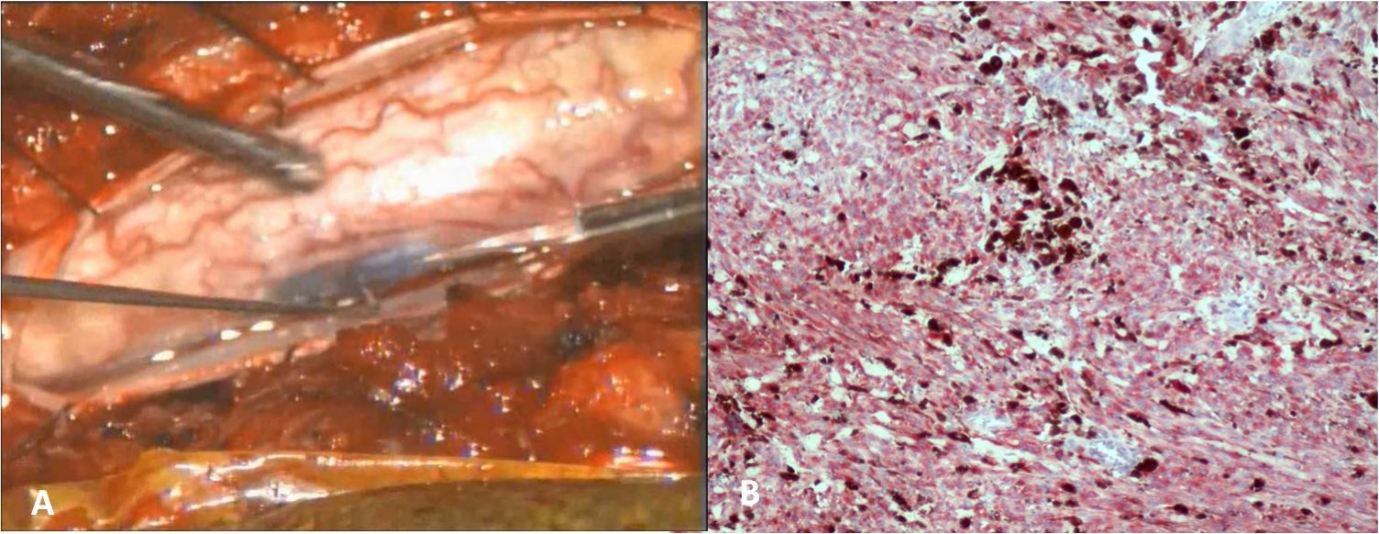

A 74-year-old woman presented complaining a several-month history of increasing thoracic back pain and left leg pain. Neurological examination demonstrated a spastic paraparetic gait and hyperreflexia of the lower limbs. Spinal magnetic resonance imaging revealed an intramedullary mass extending from T7 to T11 measuring 22 x 12 x 15 mm, slightly hyperintense on T1weighted images and hypointense on T2 weighted sequences and showed mild and heterogeneous enhancement after injection of gadolinium (Figure 1). Motor and somatosensory evoked potentials (SSEP) were recorded during surgery. A T7-T11 laminectomy and posterior midline myelotomy was performed. The exposed black and rigid tissue was removed en block (Figure 2). Gross total removal was achieved, as confirmed by MRI with and without contrast 24 hours after operation.

Figure 2.A) Intraoperative picture. B) Photomicrograph of the bleached tumor cells displaying immuno-positivity for HMB-45.

The patient had no bowel or bladder dysfunction but preexisting left hemiparesis worsened immediately after surgery. She underwent rehabilitation, and at 2 months post surgery had regained full strength. Histological examination revealed neoplasia mainly consisting of spindle-shaped monomorphic cells with clearly visible nucleoli and melanin-rich cytoplasm. It exhibits low mitotic activity, and stains positively with HMB-45 and S-100, indicating cells of melanocytic origin. The histological diagnosis was consistent with a melanocytoma.

Melanocytomas are neural crest-derived cells which are normally found within the basal layer of the epidermis and the leptomeninges that cover the base of brain and the brain stem. Moreover, the highest concentration of melanocytes is seen ventrolateral to the medulla oblongata and upper cervical levels of spinal leptomeniges. The term ‘meningeal melanocytoma’ was first proposed by Limas and Tio in 1972 based on ultrastructural features to differentiate these benign pigmented tumors from those originating from meningothelial fibroblasts. Since then, less than 100 cases have been reported in the literature. Macroscopically, melanocytoma can be dark-to-tan (Figure 3), and is commonly composed, microscopically, of nests of spindle-shaped cells with small nucleoli and eosinophilic cytoplasm. The World Health Organization has classified primary melanocytic tumors of the nervous system into diffuse melanocytosis, melanocytoma, malignant melanoma and meningeal melanomatosis . All melanin-containing tumors show presence of spindle or epithelioid cells arranged in sheets, bundles, nests or whorls. The difference between melanocytoma and melanoma is the low mitotic activity and the absence of nuclear atypia, as shown by low reactivity with Ki-67. Moreover a positive immunoreactivity for S100 protein, Vimentin, HMB- 45 favors the diagnosis of a melanocytic tumor. Malignant transformation of a melanocytoma to melanoma following complete excision has been reported in the literature. This is why the goal of the treatment should be gross total resection with preservation of neurological function. These lesions are exceedingly rare. Approximately 50% of the cases are found intracranially, mostly observed in supratentorial locations, and the other half in the spinal canal, mostly in the thoracic region. They are usually intradural and extramedullary, but can be either extradural or intramedullary. Intramedullary melanocytomas are extremely rare. In the review of the literature 16 cases described origin from thoracic region as our case and only 5 cases from cervical spine. Spinal melanocytomas are slowly growing tumors that usually present with symptoms of mass effect, such as pain, myelopathy, spastic paraparetic gait. In rare cases, however, they may have small hemorrhages and present with signs of superficial siderosis. These neoplasms are most commonly found as solitary lesions, but can present as multifocal lesions or can be disseminated along the arachnoid and dura mater.